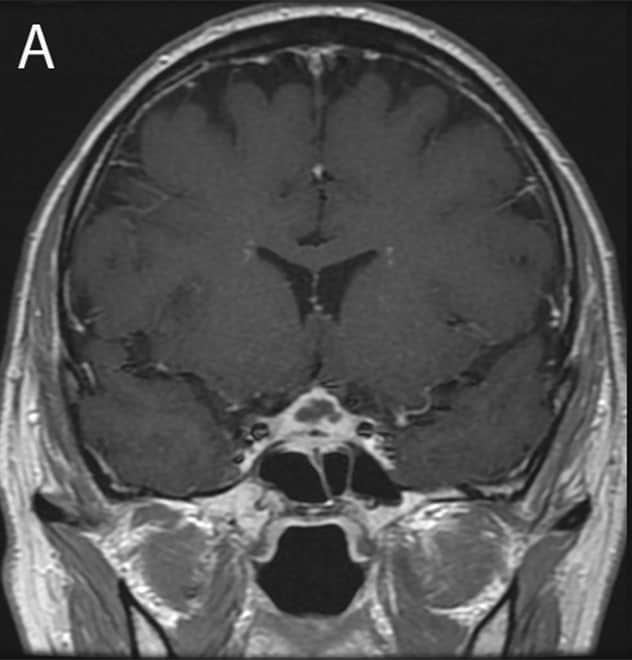

Initial presentation of soft tissue sellar mass

Initial presentation of soft tissue sellar mass

Initial presentation: 1.8 cm soft tissue sellar mass on MRI.

A water deprivation test confirmed central diabetes insipidus. A pituitary-directed head magnetic resonance imaging (MRI) revealed a 1.8 cm soft tissue mass in the sella extending into the suprasellar cistern with distortion of the optic chiasm. The mass appeared heterogeneous with low attenuation in neighboring tissue and thickening of the sphenoid air cells.